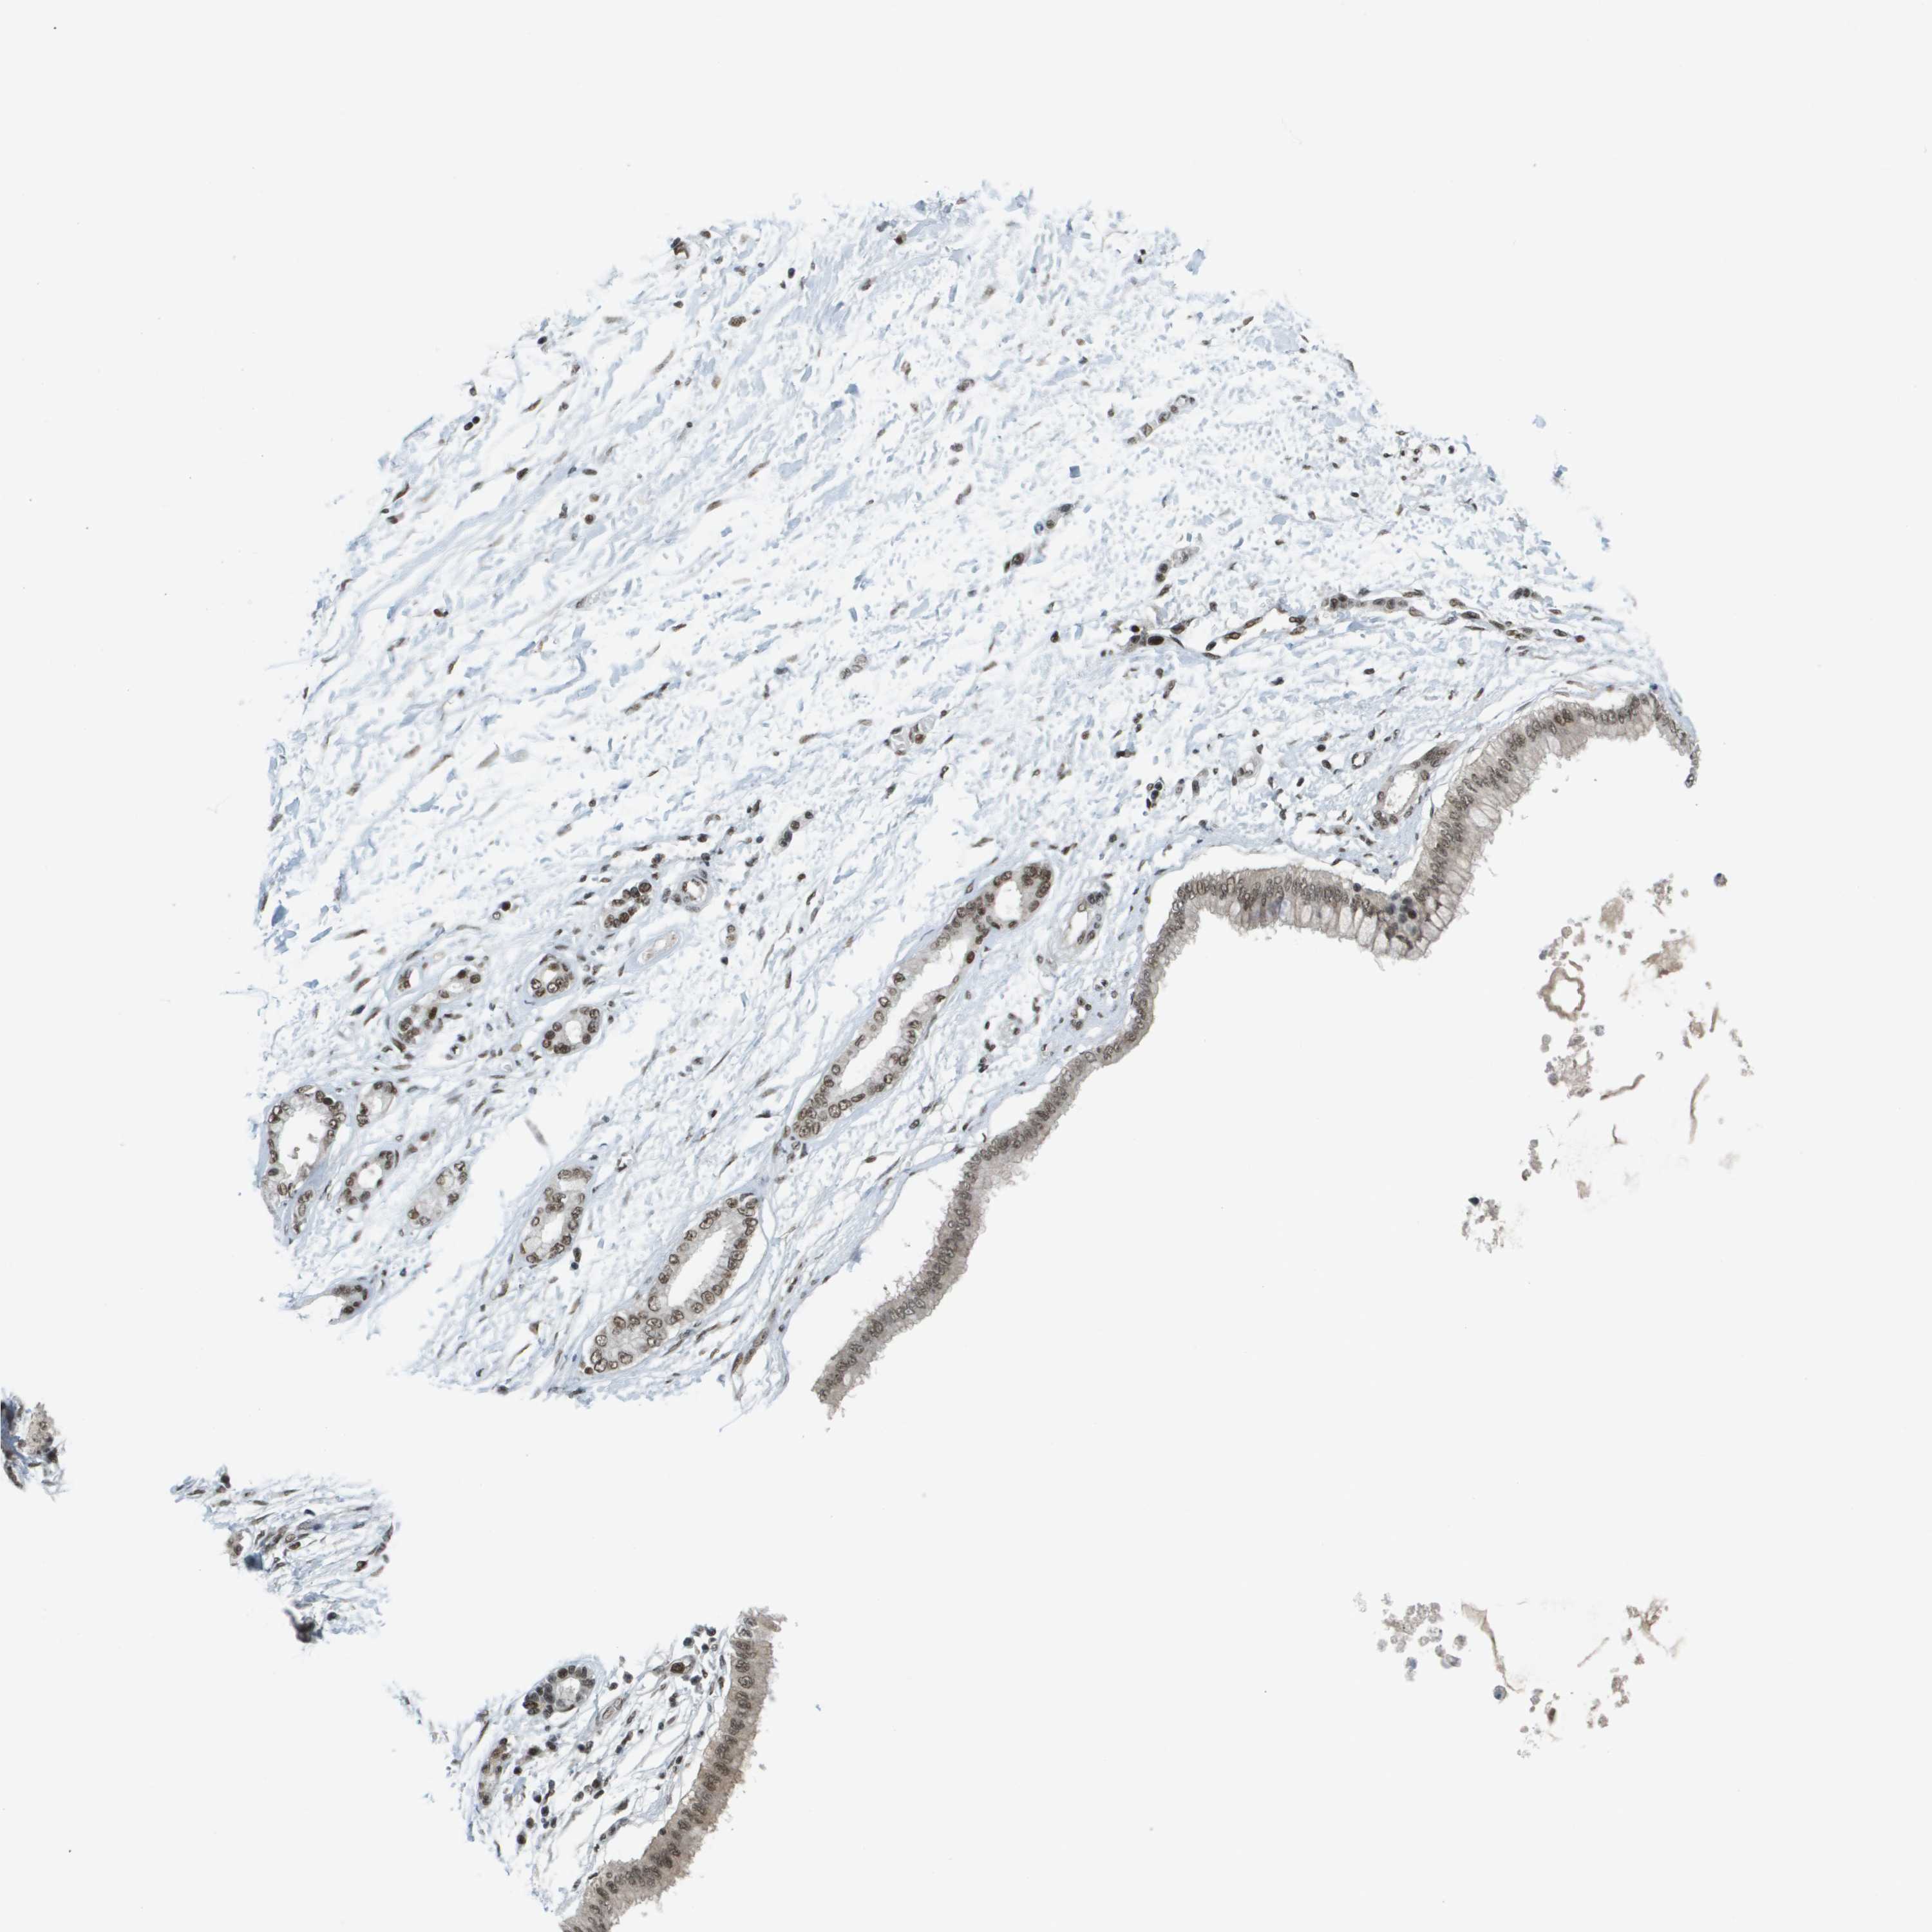

PANCREATIC CANCER - Protein expressioni

A mouse-over function shows sample information and annotation data. Click on an image to view it in a full screen mode. Samples can be filtered based on level of antibody staining by selecting one or several of the following categories: high, medium, low and not detected. The assay and annotation is described here.

Note that samples used for immunohistochemistry by the Human Protein Atlas do not correspond to samples in the TCGA dataset.

Antibody stainingi

Antibody staining in the annotated cell types in the current human tissue is reported as not detected, low, medium, or high, based on conventional immunohistochemistry profiling in selected tissues. This score is based on the combination of the staining intensity and fraction of stained cells.

Each image is clickable and will lead to virtual microscopy that enables deeper exploration of all samples and also displays staining intensity scores, fraction scores and subcellular localization as well as patient and tissue information for each sample.

Antibody HPA052757

Antibody CAB017694

Staining

High

Medium

Low

Not detected

Intensity

Strong

Moderate

Weak

Negative

Quantity

>75%

75%-25%

<25%

None

Location

Nuclear

Cytoplasmic/membranous

Cytoplasmic/membranous,nuclear

Adenocarcinoma, NOS